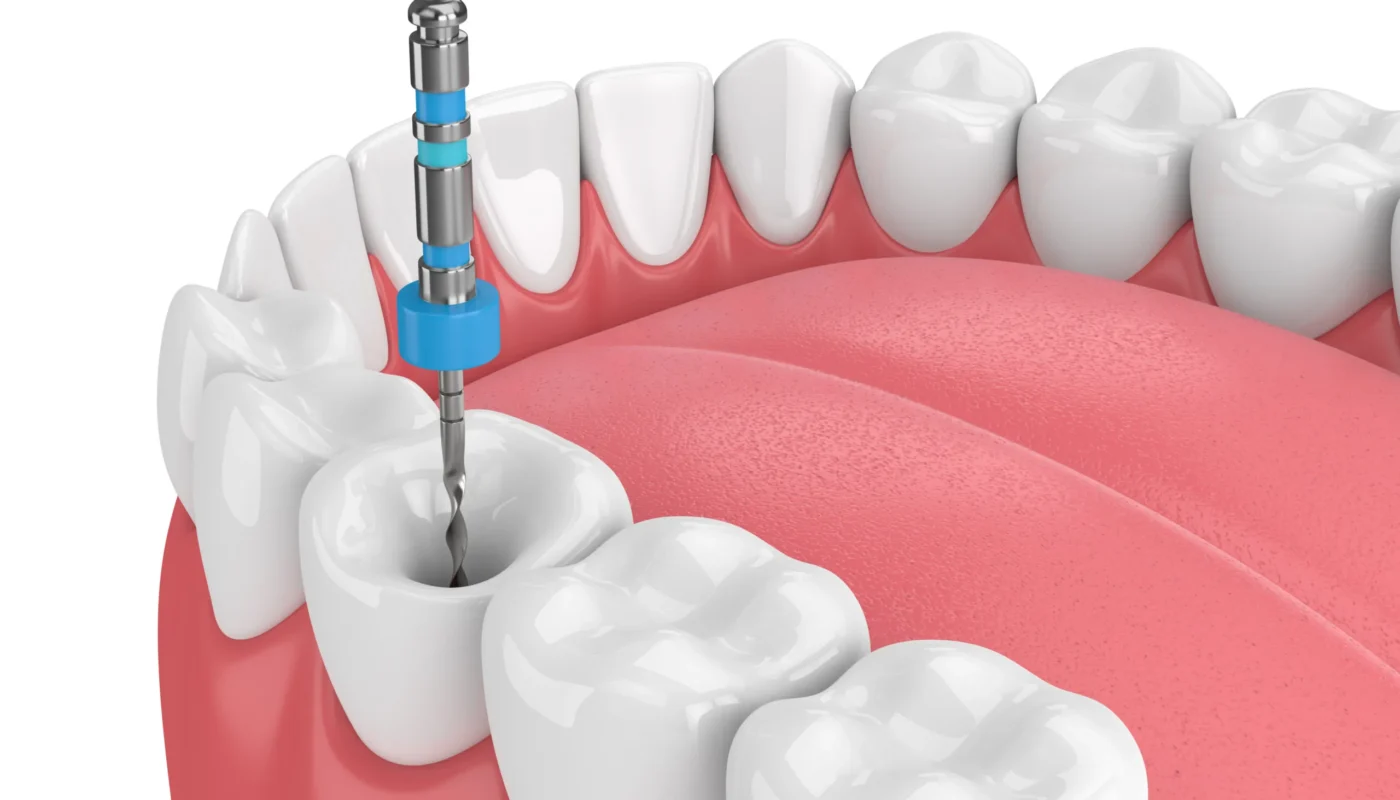

Root canal therapy treats infection inside the tooth to relieve pain and save your natural tooth. This endodontic procedure removes damaged tissue, restores strength, and helps prevent further complications.

Root canal therapy is a highly effective treatment designed to eliminate infection, relieve pain, and preserve your natural tooth. At Natalie B McCarthy, DDS, root canal therapy in Greenville NC is performed with a gentle, precise approach that prioritizes both comfort and long-term results. Endodontics, the branch of dentistry focused on the inner structures of the tooth, plays a key role in treating issues that affect the dental pulp, nerves, and surrounding tissues. Inside every tooth is a soft core made up of nerves, blood vessels, and connective tissue. When this inner portion becomes infected or damaged due to deep decay, trauma, or cracks, it can lead to significant discomfort and sensitivity. Common symptoms include persistent tooth pain, sensitivity to hot or cold, swelling, and tenderness when chewing. Without treatment, the infection can worsen and may eventually lead to tooth loss. Root canal therapy offers a way to stop the infection while preserving the natural structure of your tooth. During the procedure, the infected tissue is carefully removed, and the inside of the tooth is thoroughly cleaned and disinfected. The space is then filled with a specialized material to restore stability and prevent further infection. In most cases, a dental crown is placed afterward to strengthen and protect the tooth, allowing it to function normally once again. Root canal treatment typically requires only one or two visits and provides lasting relief for patients dealing with tooth pain. This approach not only eliminates discomfort but also helps maintain proper alignment and overall oral health.